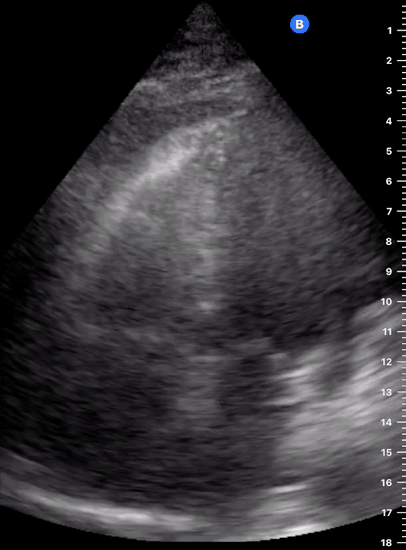

Effusion: is there a pericardial or pleural effusion?

Pericardial effusion is a continuum and can potentially evolve into haemodynamic collapse. Tamponade physiology is detectable earlier with ultrasound than with traditional physical examination, and it has been demonstrated that PoCUS improves mortality in penetrating cardiac trauma. Timely and accurate diagnosis is, therefore, vital.

THE VIEWS

The subxiphoid view is the most reliable for detecting pericardial effusion. Still, it is ideal to obtain different views not to miss a focal effusion as small amounts of fluid can lead to tamponade physiology. Tamponade does not link strictly to the size of the effusion, but correlates more with the speed of onset, causes, and haemodynamic effects.

PITFALLS & PLEURAL EFFUSIONS

A common error is to confuse a pericardial fat pad with effusion. Fatty tissue has a heterogeneous echotexture, moving in coordination with the myocardium, and it cannot be tracked around the heart, especially posteriorly and to the apex. Another pitfall is misinterpreting a pleural effusion as a pericardial effusion. However, they can be differentiated by their relationship to the descending aorta. Pericardial effusion may be seen between the aorta and the LV free wall, whereas pleural effusions are posterior to the descending aorta. Lastly, other causes, namely hypovolaemia and large pleural effusions, can cause RA and RV collapse.

CARDIAC TAMPONADE

Progressively rising pressure translates into evolving tamponade, and this accompanies a series of ultrasound findings:

Initially, the RA collapses during ventricular systole (closed AV valves).

Followed by RV collapse in ventricular diastole (open AV valves).

Ultimately leading to LV collapse.

In addition, the presence of a non-collapsible, plethoric IVC is one of the most sensitive signs of tamponade, and a finding easy to visualise. Conversely, a pericardial effusion in a haemodynamically stable patient with a collapsible IVC is unlikely to represent tamponade.

Chamber collapse can be assessed in M-mode, where the collapsing RV is seen as a notch that takes place right after the mitral valve opening and before its closure (during diastole).